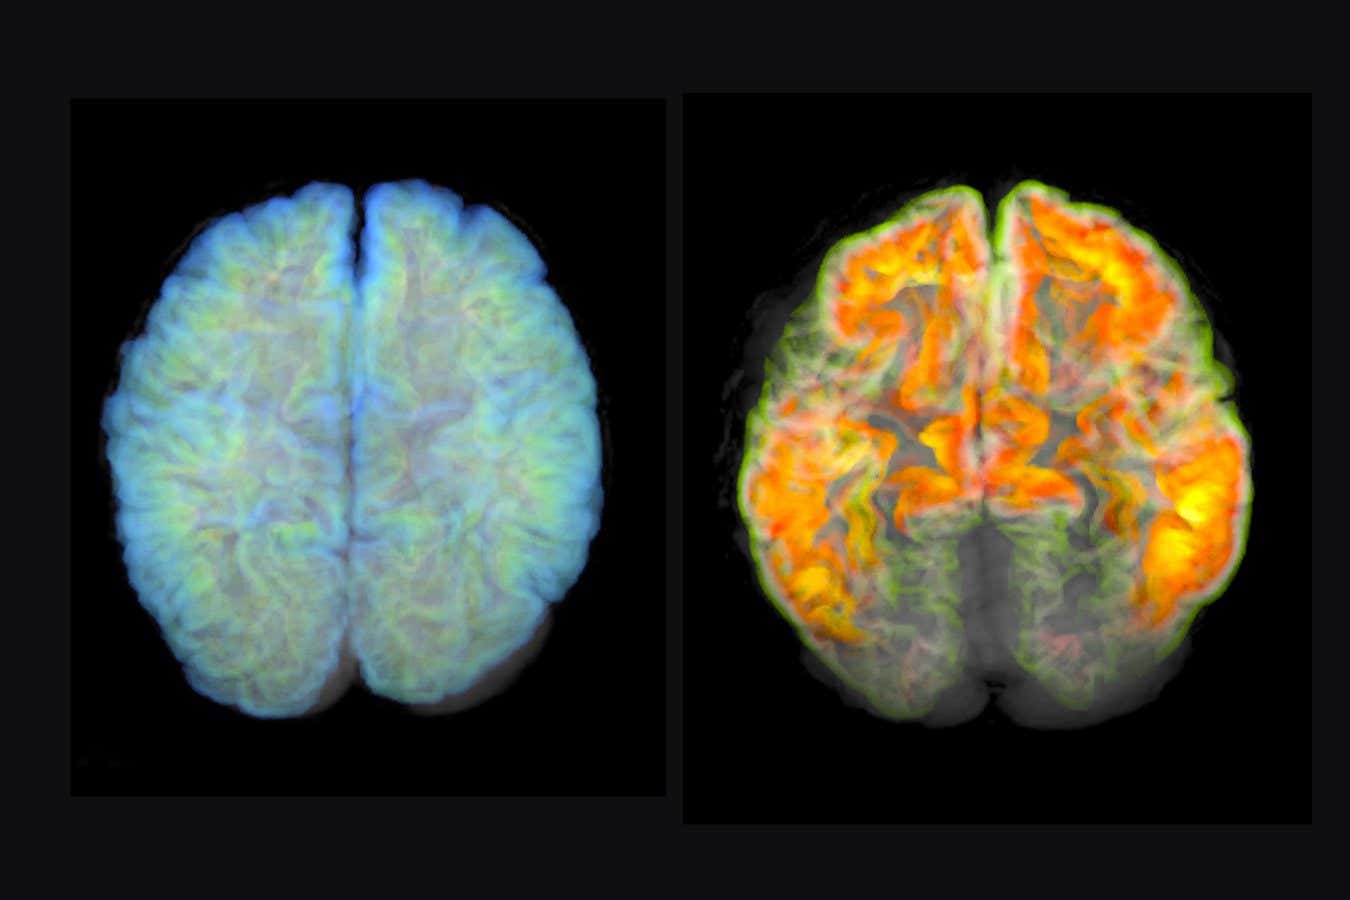

MRI scans of a healthy brain (left) and a brain with amyloid plaque deposits (right), a sign of Alzhiemer’s disease MARK AND MARY STEVENS NEUROIMAGING AND INFORMATICS INSTITUTE/SCIENCE PHOTO LIBRARY

Some hailed 2023 as the beginning of a turning point in our efforts to combat Alzheimer’s disease. Two countries – the US and Japan – approved a drug called lecanemab, the first treatment that actually slows the condition’s progression, rather than just easing its symptoms. Many other countries, including the UK and Australia, are now considering following suit, but the drug isn’t without its critics.